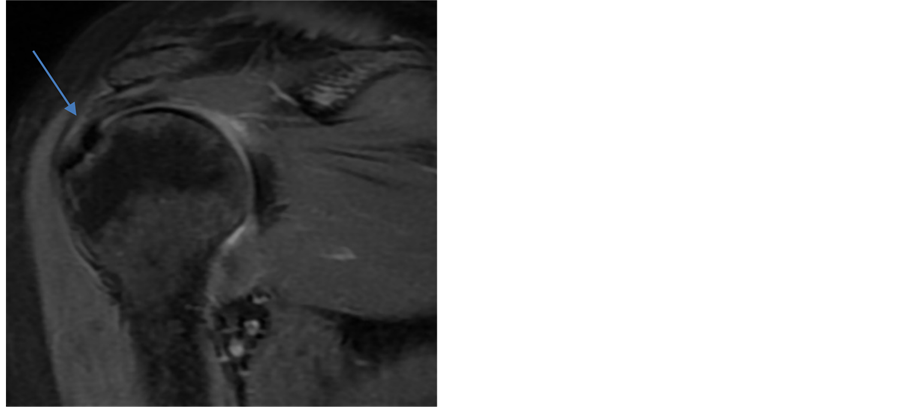

Waldt et al. [25] showed that at muscle tendon margin differentiation among fibre tearing, tendinitis, tendinopathy, synovial changes and superficial fraying is difficult so the diagnosis of small PTT are restricted. There occurs limitation to find out obvious focal discontinuity or defect depending on the presence of high signal intensity only which lead to underestimation of true PTT [26] . We experienced reference standard was more dependent upon MRI findings, especially while detecting PTT (Figure 3). Few false negatives were read as either reactive changes due to tendinopathy, tendinosis or calcific tendinitis and still it is not uncommon even using high-field MRIs [24] . Using high-field MRI scanners, improvement in identifying the shoulder pathology has been shown by arthrograms [24] . In our study, none of the cases had been undergone arthrogram. There were seven false positive PTT and if these PTT were regarded as true positive then the sensitivity, specificity, accuracy, positive predictive value, negative predictive value of MRI would increase as that of FTT. Thus the imperfect standard bias and selection bias has hugely decreased the accuracy of MRI in detection of PTT.

Figure 3. Coronal T2 weighted fat-suppression MR image show a partial- thickness tears (arrow) at the insertion of supraspinatus tendon which were wrongly interpreted as tears for thickened tendon (false-positive partial- thickness rotator cuff tears). This finding was confirmed as no tears in surgery. Also shoulder joint effusion can be seen.